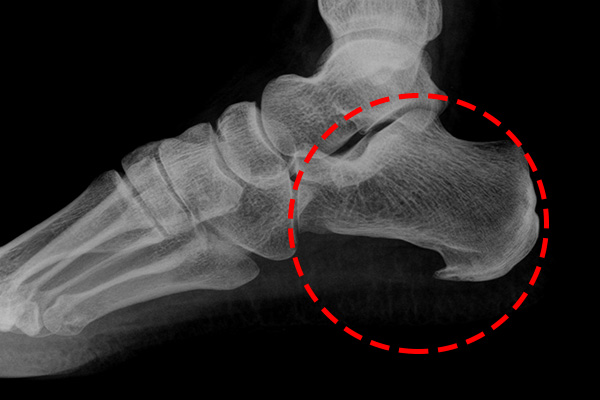

통증이 발생하는 이유는 족저 근막이 과도하게 늘어나거나 손상되기 때문입니다. 족저 근막은 발의 아치를 지탱하는 역할을 하며, 이곳에 지나치게 많은 압력이 가해지면 염증이 발생하게 됩니다. 통증이 지속되는 경우, 걷기나 서 있는 것만으로도 불편함을 느낄 수 있습니다.

네 번째로 통증이 특정 위치에서 집중적으로 느껴지는 증상이 있습니다. 대개 발바닥 중앙, 특히 아치 부분이 가장 아픈 곳입니다. 그러나 개인차가 있을 수 있으며, 종종 발꿈치 쪽이나 발목으로 방사되는 통증을 경험하는 경우도 많습니다.